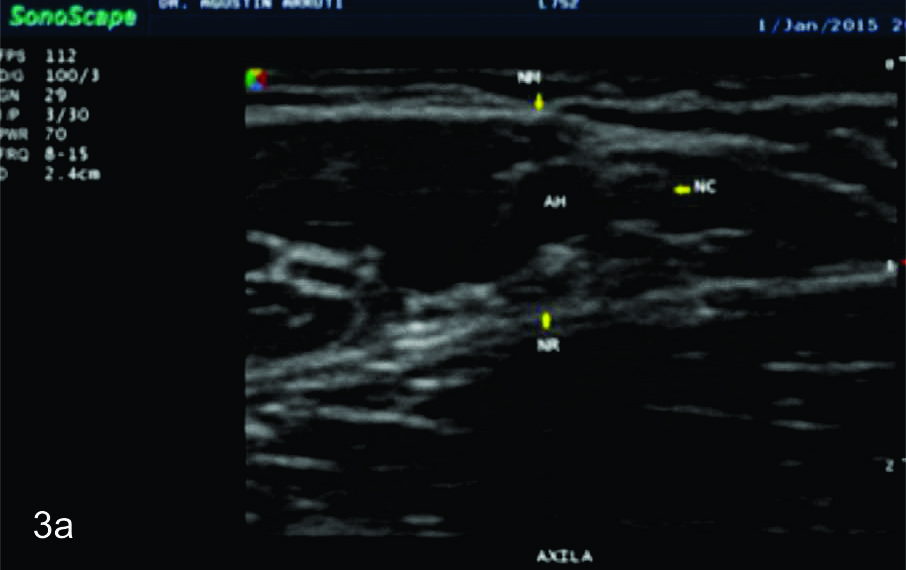

Figura 7

Nervio cubital

Serie de cortes axiales del nervio cubital desde su origen a nivel del hueco axilar hasta su terminación a nivel del canal de Guyon. Se identifica el mismo señalado por flechas amarillas y con las letras NC. AH-arteria humeral, PC- músculo prondador cuadrado, P- hueso pisciforme, Línea roja- ligamento anular del carpo, Línea amarilla- túnel de Guyon, Flecha azul- Arteria cubital-. A-tercio distal antebrazo, B- canal de Guyon.